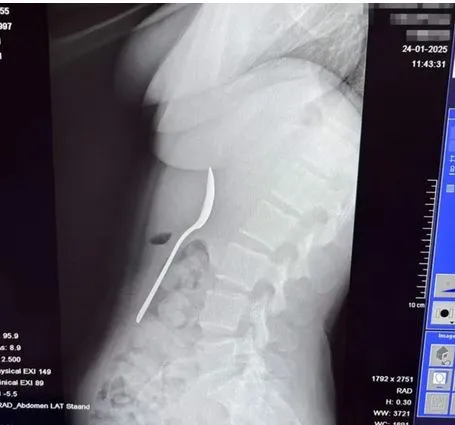

Необичаен случай в Белгия приключи със незабавна здравна интервенция. Млада жена инцидентно погълнала 17-сантиметрова лъжица, до момента в който похапвала кисело мляко вкъщи.

„ Сложих лъжицата в устата си, с цел да имам свободни ръце и да отговоря на известие. Точно тогава Марли реши да скочи върху мен. Стреснах се, дръпнах глава обратно и преди да осъзная – лъжицата беше заседнала в гърлото ми “, спомня си тя.

Лекарите открили, че лъжицата е прекомерно огромна, с цел да премине естествено през организма, и възнамерявали гастроскопия за изваждането ѝ. През нощта преди процедурата дамата усещала придвижването на предмета и изпитвала мощен дискомфорт, написа Metro.

Два дни по-късно лъжицата била сполучливо отстранена под локална анестезия. По време на процедурата лекарите трябвало да я завъртят, което предизвикало дребен стомашен кръвоизлив. Въпреки това Рейми се възстановила без трайни увреждания, въпреки да имала краткотрайно възпалено гърло и сензитивен корем.